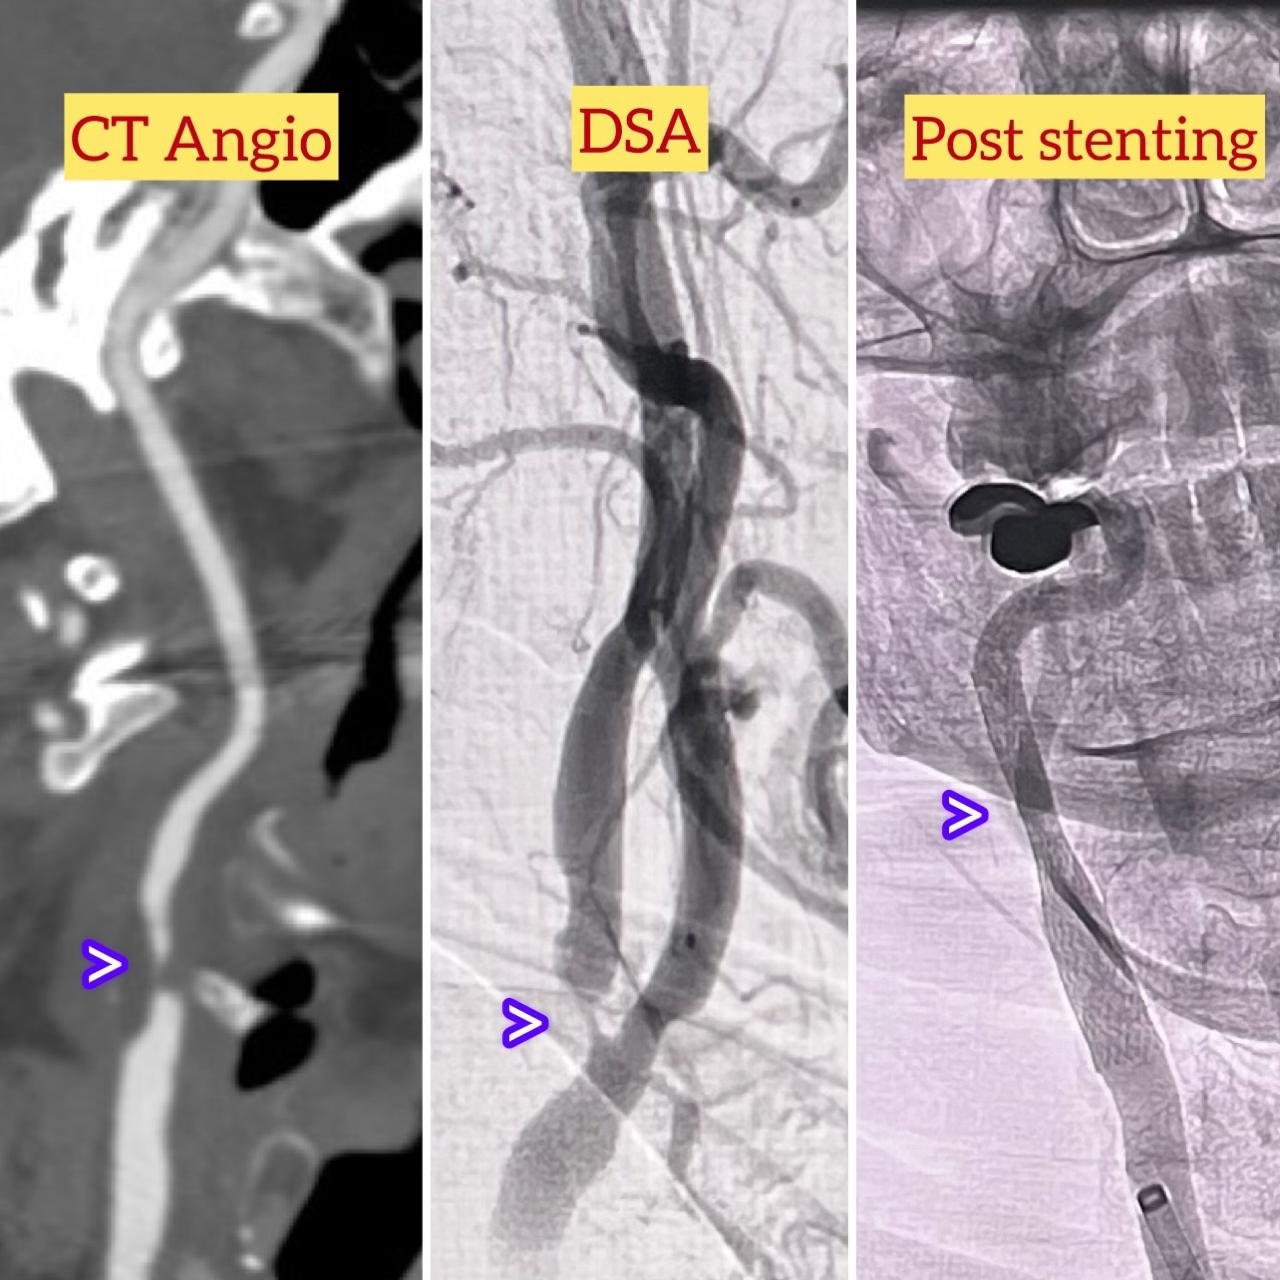

Carotid Artery Stenting